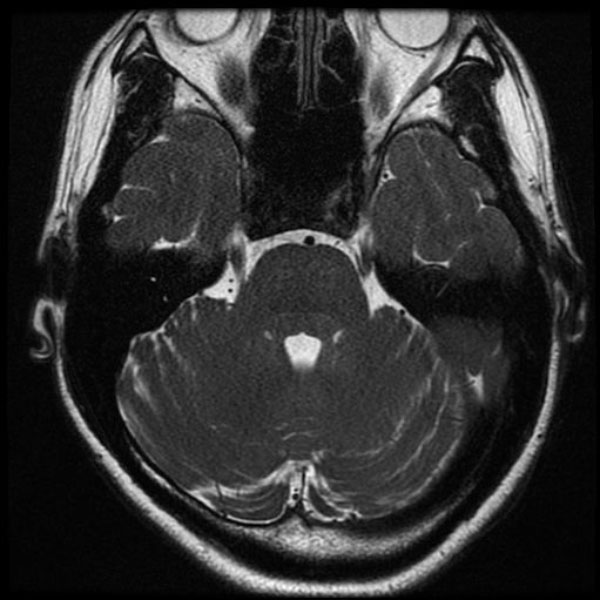

手術前

(MR1)